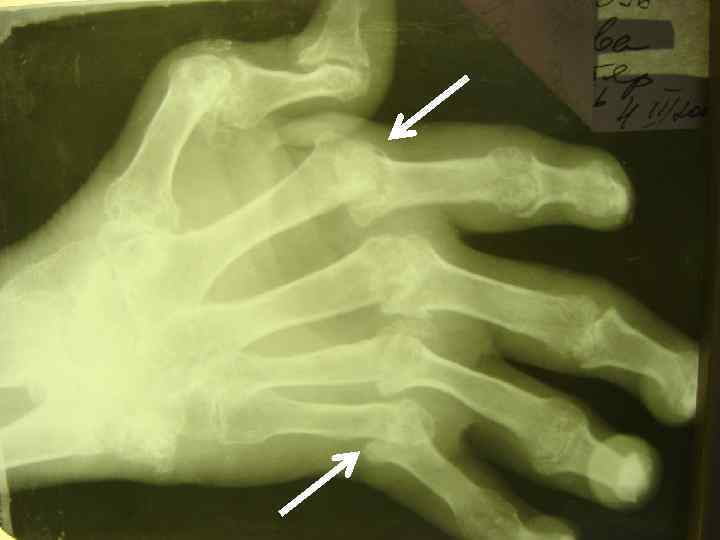

ДИАГНОСТИЧЕСКИЕ КРИТЕРИИ РА (АРА, 1987, 1998) l l l 5. НАЛИЧИЕ ПОДКОЖНЫХ УЗЛОВ В ОБЛАСТИ ЕСТЕСТВЕННЫХ КОСТНЫХ УТОЛЩЕНИЙ И РАЗГИБАТЕЛЬНЫХ ПОВЕРХНОСТЕЙ КОНЕЧНОСТЕЙ ИЛИ ПЕРИАРТИКУЛЯРНО (РЕВМАТОИДНЫЕ УЗЕЛКИ). 6. ОБНАРУЖЕНИЕ РЕВМАТОИДНОГО ФАКТОРА В СЫВОРОТКЕ КРОВИ ИЛИ СИНОВИАЛЬНОЙ ЖИДКОСТИ. 7. ТИПИЧНЫЕ РЕНТГЕНОЛОГИЧЕСКИЕ ИЗМЕНЕНИЯ: ОКОЛОСУСТАВНОЙ ОСТЕОПОРОЗ, ЭРОЗИВНЫЙ АРТРИТ.

R-ЛОГИЧЕСКИЕ СТАДИИ РА (STEINBROCKER, 1949) l СТАДИЯ I — ОКОЛОСУСТАВНОЙ ОСТЕОПОРОЗ БЕЗ l СТАДИЯ II — НЕЗНАЧИТЕЛЬНОЕ СУЖЕНИЕ l СТАДИЯ III — ЗНАЧИТЕЛЬНОЕ РАЗРУШЕНИЕ ХРЯЩА И l СТАДИЯ IV — ПРИЗНАКИ III СТАДИИ + АНКИЛОЗ ДЕСТРУКТИВНЫХ ИЗМЕНЕНИЙ. СУСТАВНОЙ ЩЕЛИ, ЕДИНИЧНЫЕ УЗУРЫ КОСТЕЙ. КОСТИ: ВЫРАЖЕННОЕ СУЖЕНИЕ СУСТАВНОЙ ЩЕЛИ, МНОЖЕСТВЕННЫЕ УЗУРЫ, ПОДВЫВИХИ, КОСТНЫЕ КИСТЫ.